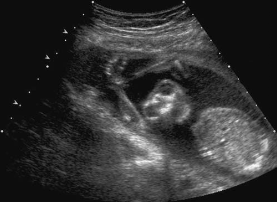

An asymptomatic patient arrives for a second- trimester fetal surveillance examination. A sagittal image of the fetal body is most suspicious for:

sacrococcygeal teratoma

Associated findings with this abnormality include:

hydronephrosis